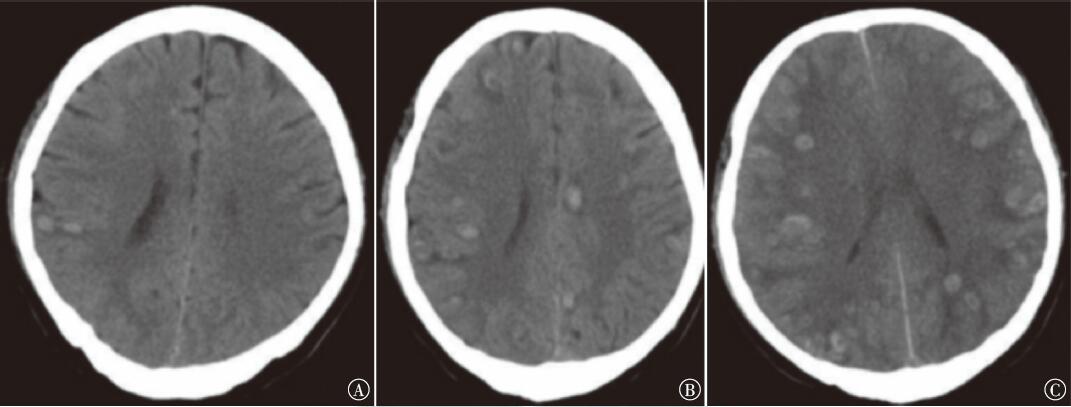

慢性中性粒细胞白血病(CNL)是一种罕见的侵袭性BCR-ABL融合基因阴性的骨髓增殖性肿瘤,起病隐匿,临床表现缺乏特异性,易与其他中性粒细胞增多的疾病混淆,易误诊。CNL增生的白血病细胞浸润大脑导致急性广泛脑出血属急危重症,较罕见。现报道1例CNL急性脑出血病例,以警示临床。

邢明泉, 孙晓星, 张言荣, 张司琪, 吴维霞, 葛洪峰. “颅内开花”——慢性中性粒细胞白血病罕见急性脑出血1例[J]. 国际肿瘤学杂志, 2024, 51(9): 606-608.